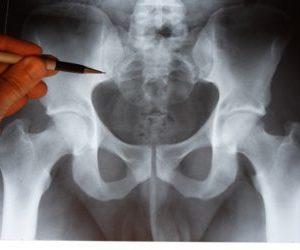

Кроме того, пациентам рекомендуется рентгенография пояснично-крестцового отдела позвоночника, что позволяет визуализировать участки травм и остеопороза, а также выявить признаки остеохондроза копчика.